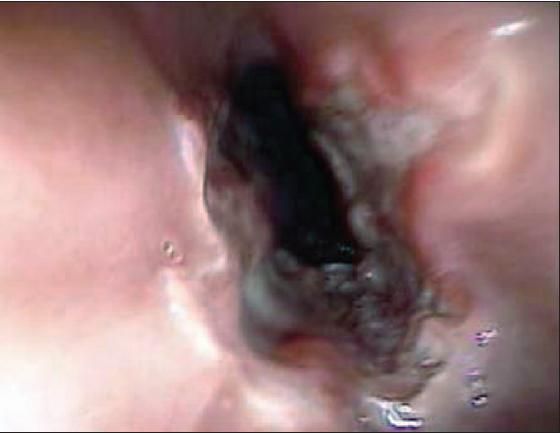

The patient's upper endoscopy findings are shown.

Case 1: The endoscopic findings showed 2 adjacent ulcerations (or kissing lesions) 2 cm in diameter in the mid esophagus at the level of the aortic arch narrowing.